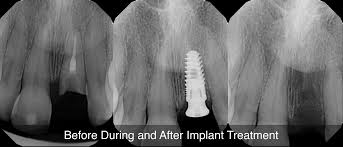

If the root canal treatment fails and you need an extraction, this is the time to replace it and not before. The root canal treatment becomes necessary when the aim is to repair and save teeth that are either badly infected or decayed. How is a root canal done? There are no pain signals but that tooth is still dead and needs a rootcanal treatment or removal. At which case you would need a dental bridge or a tooth implant. If you do not get a root canal when you need one, the infection can spread from the tooth in question to the gum and jawbone surrounding how long does a root canal take? A root canal or tooth extraction. Many ask, should i have a root canal or extraction? when this happens, there are two options for addressing the issue:

Nevertheless, you will experience a greater discomfort after root canal treatment compared to extraction. Eventually, the tooth will become loose and need extracting. If you've been told you need a root canal or are scheduled for one soon, you're in the right place. That is not to say that you cannot have pain following a root canal. Read about root canal cost, pain, symptoms, signs, and recovery. They are relatively simple procedures and do not often involve a large amount of pain in addition, getting a timely root canal often means that you are able to save the tooth itself, which is obviously preferable to tooth extraction. For a root canal to be successful, the canals must be thoroughly cleaned and sealed. These procedures have various pros and cons, but the general consensus from dental professionals is that it's best to save the tooth whenever.